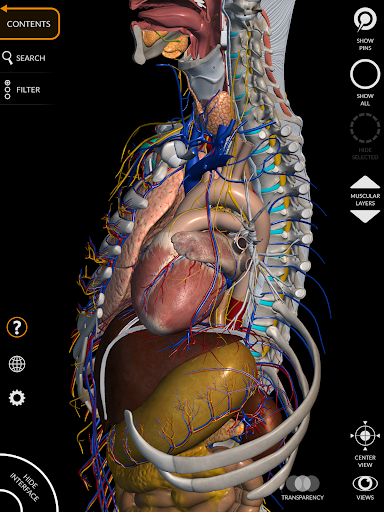

"Anatomy 3D Atlas" memungkinkan Anda mempelajari anatomi manusia dengan cara yang mudah dan interaktif.

Melalui antarmuka yang sederhana dan intuitif, Anda dapat mengamati setiap struktur anatomi dari sudut mana pun.

Model 3D anatomi sangat terperinci dan memiliki tekstur hingga resolusi 4k.

Pembagian berdasarkan wilayah dan tampilan yang telah ditetapkan sebelumnya memudahkan pengamatan dan studi bagian tunggal atau kelompok sistem dan hubungan antara organ yang berbeda.

MODEL ANATOMI 3D

• Sistem muskuloskeletal

• Sistem kardiovaskular • Sistem

saraf • Sistem pernapasan • Sistem pencernaan • Sistem urogenital (pria dan wanita) • Sistem endokrin • Sistem limfatik • Sistem mata dan telinga FITUR • Antarmuka yang sederhana dan intuitif • Putar dan perbesar setiap model dalam ruang 3D • Opsi untuk menyembunyikan atau mengisolasi satu atau beberapa model yang dipilih • Filter untuk menyembunyikan atau menampilkan setiap sistem • Fungsi pencarian untuk menemukan setiap bagian anatomi dengan mudah • Fungsi penanda untuk menyimpan tampilan khusus • Rotasi cerdas yang menggerakkan pusat rotasi secara otomatis • Fungsi transparansi • Visualisasi otot melalui tingkat lapisan dari yang superfisial hingga yang terdalam • Dengan memilih model atau pin, istilah anatomi terkait akan muncul • Deskripsi otot: asal, • Tampilkan/ Sembunyikan antarmuka UI (sangat berguna dengan layar kecil) MULTIBAHASA • Istilah anatomi dan antarmuka pengguna tersedia dalam 11 bahasa: Latin, Inggris, Prancis, Jerman, Italia, Portugis, Turki, Rusia, Spanyol, Mandarin, Jepang, dan Korea • Istilah anatomi dapat ditampilkan dalam dua bahasa secara bersamaan PERSYARATAN SISTEM • Android 8.0 atau yang lebih baru, perangkat dengan RAM minimal 3GB Reversi